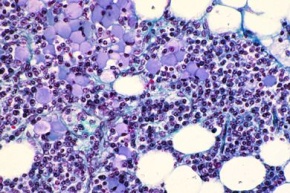

Mikropräparat - Mastzellen im Omentum der Ratte. Färbung mit Toluidinblau-Paracarmin

Mikropräparat - Mastzellen im Omentum der Ratte. Färbung mit Toluidinblau-Paracarmin